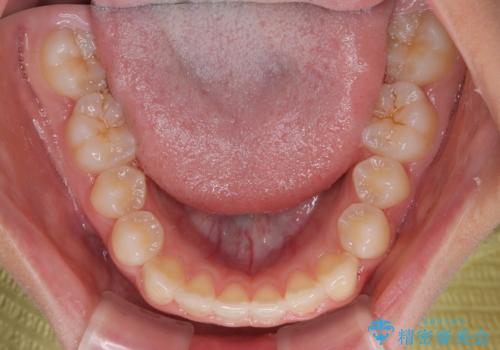

- 前歯の隙間を気にして来院された患者様です。

口元の突出感があり、小臼歯4本を抜歯して口元を引っ込める矯正治療も提案しましたが、本人は口元の突出感は気になっていないとのことで、インビザラインにて隙間やデコボコを改善することとしました。

軽度の歯列不正であったため、廉価版のインビザライン・モデレートパッケージにて治療を終えることができました。